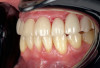

Whereas erosion is the result of chemical dissolution of tooth structure and abrasion is the loss of tooth structure caused by contact with external objects other than opposing teeth (eg, via vigorous toothbrushing), attrition is a wear process caused by direct tooth-to-tooth contact (Figure 1 and Figure 2).7 The most common cause of attrition is bruxism.8 Characterized by the involuntary gnashing, grinding, or clenching of teeth, bruxism is usually an unconscious activity, which may occur both during sleep (sleep bruxism) or when the individual is awake (awake bruxism).9-11 According to the American Dental Association, severe bruxing can cause extensive damage to the teeth and supporting structures.12

Fig 1. Severe attrition of teeth Nos. 5 through 12.

Figure 1

Fig 2. Right lateral view, showing severe attrition of teeth Nos. 5 though 12, abfraction lesions on teeth Nos. 6 and 11,

and overjet.

Figure 2